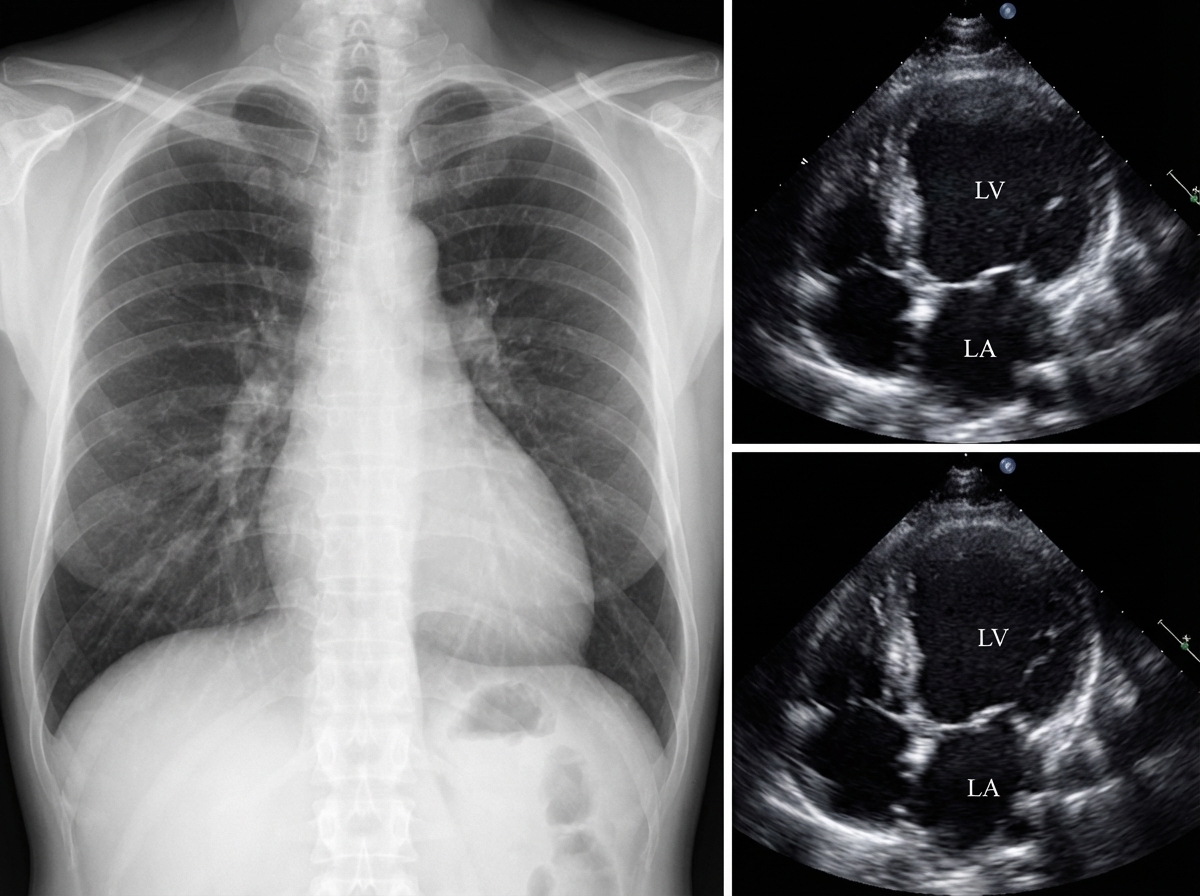

Explanation: ***Doxorubicin*** - **Doxorubicin** (anthracycline) causes **dose-dependent cardiotoxicity** leading to **dilated cardiomyopathy** and reduced ejection fraction as shown in the image. - The mechanism involves **free radical damage** to cardiac myocytes with a cumulative dose limit of ~**550 mg/m²**; **dexrazoxane** can be used for cardioprotection. *Clarithromycin* - This **macrolide antibiotic** primarily causes **QT prolongation** and potential arrhythmias, not structural heart changes. - Does not cause **cardiomegaly** or **dilated cardiomyopathy** as seen in the image. *Dexamethasone* - This **corticosteroid** causes **Cushingoid features** including moon face, buffalo hump, and central obesity. - Cardiovascular effects include **hypertension** and **fluid retention**, but not dilated cardiomyopathy. *Efavirenz* - This **NNRTI antiretroviral** causes **CNS effects** (vivid dreams, dizziness) and **neuropsychiatric symptoms**. - Associated with **lipodystrophy** and metabolic changes, but not cardiac structural abnormalities.